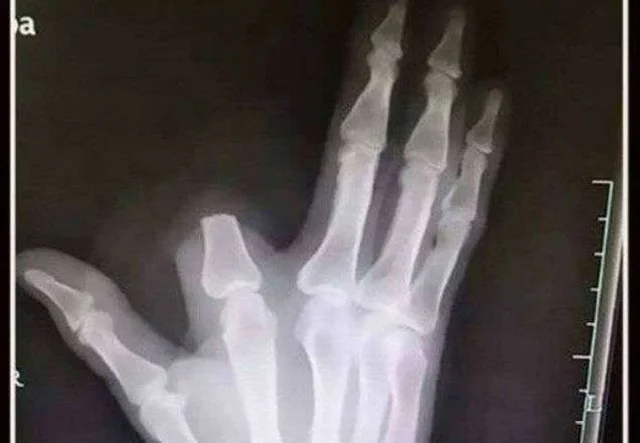

Taken by despair, Zhang decided to amputate his finger to contain the supposed spread of the poison. He then traveled about 80 kilometers to the nearest hospital, where he received the surprising news: the snake was not poisonous.

According to doctors, the animal identified was a Deinagkistrodon, a common species in the region, but without lethal venom. The heroic and hasty gesture ended up resulting in permanent damage.

To make matters worse, the elderly man left his amputated finger at the site of the bite, which made any attempt at reimplantation impossible. “If he had brought the limb, we could have performed a reimplantation surgery with a good chance of success,” explained one of the surgeons.